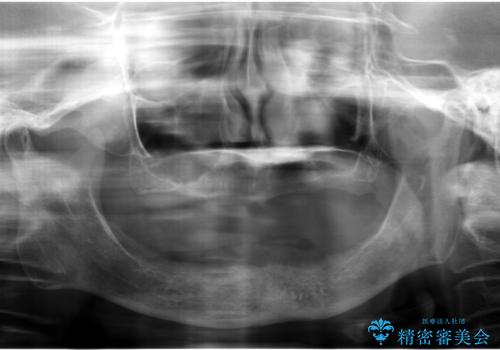

- 上の入れ歯の歯がとれてしまったこと・ゆるくてはずれてしまうことを主訴に来院された患者様です。

精査したところ、長年使用されていた入れ歯は劣化し、人工歯の脱離及び適合不良を認めました。

患者様のご希望により、上顎金属床義歯の新製を行いました。

適合を良くするため、咬座印象も行いました。